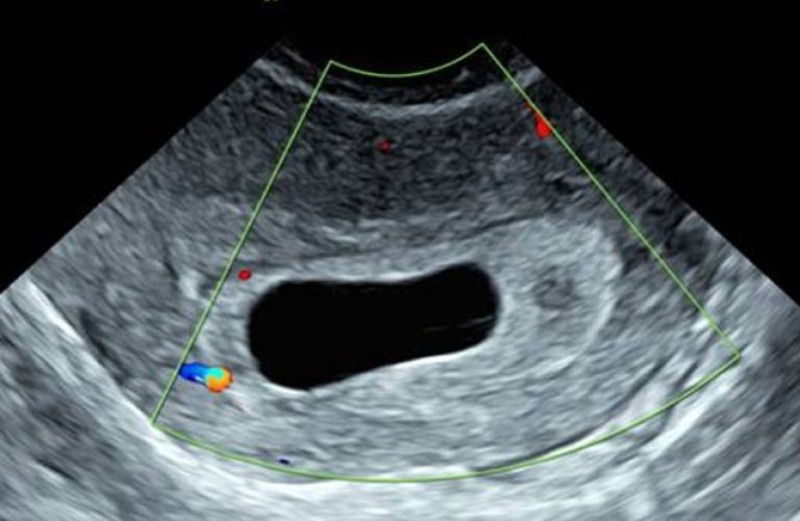

Hiện tượng xuất hiện yolksac trong siêu âm thai là dấu hiệu sớm cho thấy phôi thai đang phát triển bình thường trong tử cung. Yolksac thường được nhìn thấy ở tuần thai thứ 5 – 6 thông qua siêu âm đầu dò, xuất hiện dưới dạng một vòng tròn nhỏ, sáng bên trong túi thai. Sự có mặt của yolksac chứng tỏ quá trình thụ tinh và làm tổ đã thành công, là bước quan trọng trước khi quan sát thấy tim thai. Nếu sau tuần thứ 6 túi thai không xuất hiện yolksac, bác sĩ có thể nghi ngờ thai ngoài tử cung hoặc thai lưu.

Yolksac trong siêu âm thai hoàn toàn không nguy hiểm mà ngược lại còn là dấu hiệu tích cực cho thấy thai đang phát triển bình thường. Đây là cấu trúc tự nhiên và cần thiết trong giai đoạn đầu của thai kỳ, giúp nuôi dưỡng phôi khi nhau thai chưa hoàn thiện. Tuy nhiên, nếu yolksac có hình dạng méo mó, quá to hoặc quá nhỏ (thường >6 mm hoặc <2 mm) có thể là dấu hiệu cảnh báo bất thường trong quá trình phát triển của thai nhi. Khi bác sĩ phát hiện yolksac bất thường, thường sẽ chỉ định theo dõi sát và kiểm tra lại bằng siêu âm ở các tuần tiếp theo.

Thông thường, túi noãn hoàng có độ dày dưới 5 mm. Nếu yolksac dày hơn 5 mm hoặc có hình dạng bất thường, nguy cơ hình thành phôi thai không bình thường sẽ tăng cao. Điều này đồng nghĩa với việc tỷ lệ sảy thai trong tam cá nguyệt đầu tiên cũng cao hơn so với bình thường. Trong trường hợp yolksac quá dày hoặc bất thường, bác sĩ chuyên khoa sẽ theo dõi sát sao tình trạng sức khỏe của mẹ và thai nhi. Mẹ bầu có thể được chỉ định thực hiện thêm các biện pháp hỗ trợ y tế nhằm giảm nguy cơ sảy thai và duy trì thai kỳ ổn định.